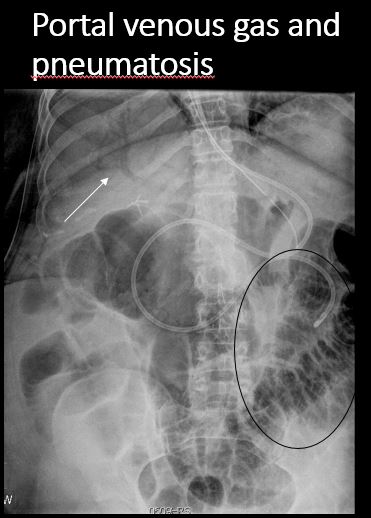

There is air in the wall of the stomach. |

No | NA |

There is air in the wall of the small or large bowel. |

There is portal venous or other intravascular gas. |